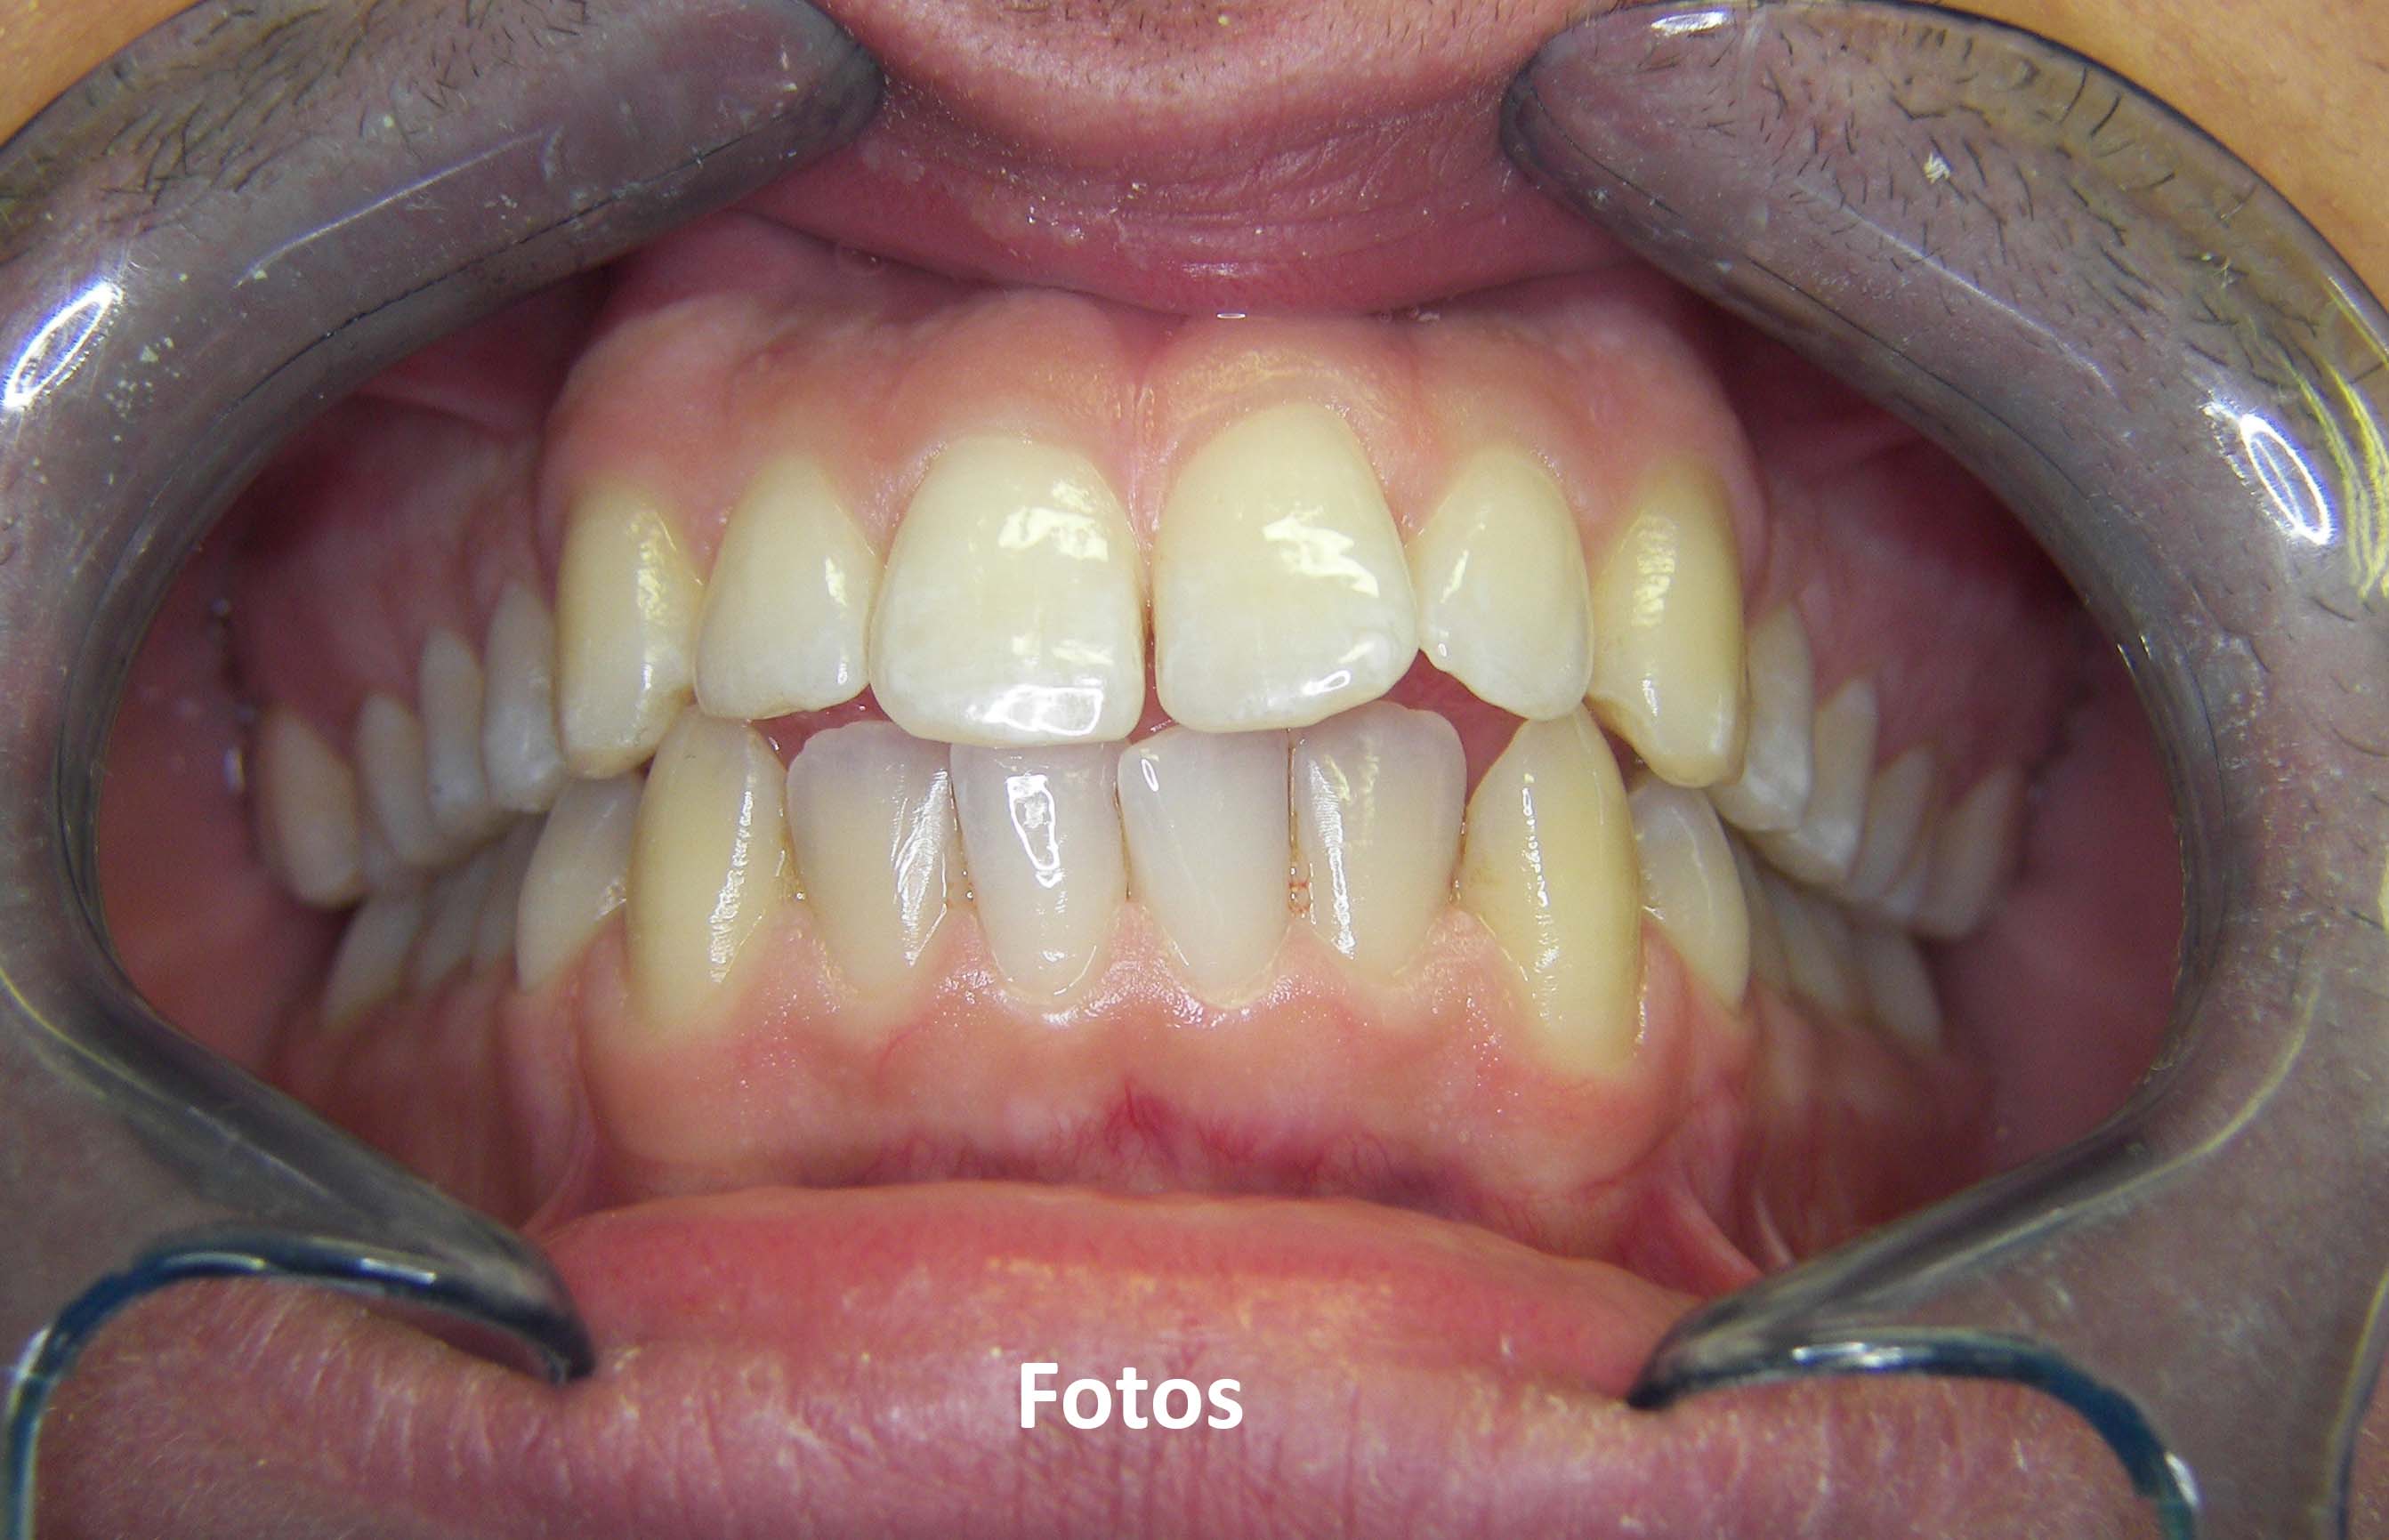

• Photos

Urgent treatments are executed if necessary as in the case on the left.